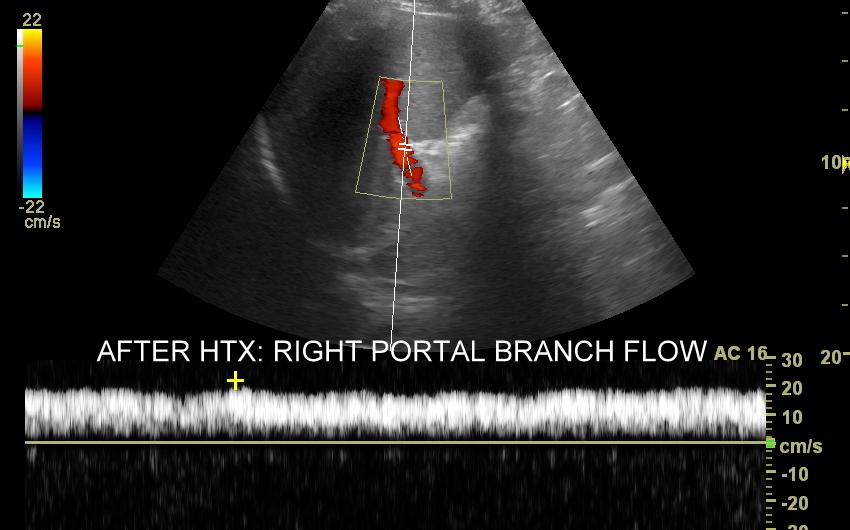

Ocena USG wątroby po przeszczepie, w tym Doppler przepływy wątrobowe, wykonywana jest zarówno w bezpośrednim szpitalnym okresie po zabiegu transplantacji, jak i w trakcie regularnej oceny ambulatoryjnej. W ramach badania sprawdzane są cechy ewentualnego odrzucania przeszczepu lub jego zapalenia, prawidłowość unaczynienia wątroby, szczelność połączeń tętniczych, żylnych oraz dróg żółciowych, a także ewentualne oznaki zwężenia lub niedrożności tychże połączeń. Interdyscyplinarna Pracownia USG prowadzona od 2011 r. przez dr Tomasza Szczepańskiego, pierwotnie w Opiece Medycznej Golden Care, jest jedną z niewielu instytucji we Wrocławiu i na Dolnym Śląsku wykonujących ocenę pacjentów po przeszczepach wątroby.